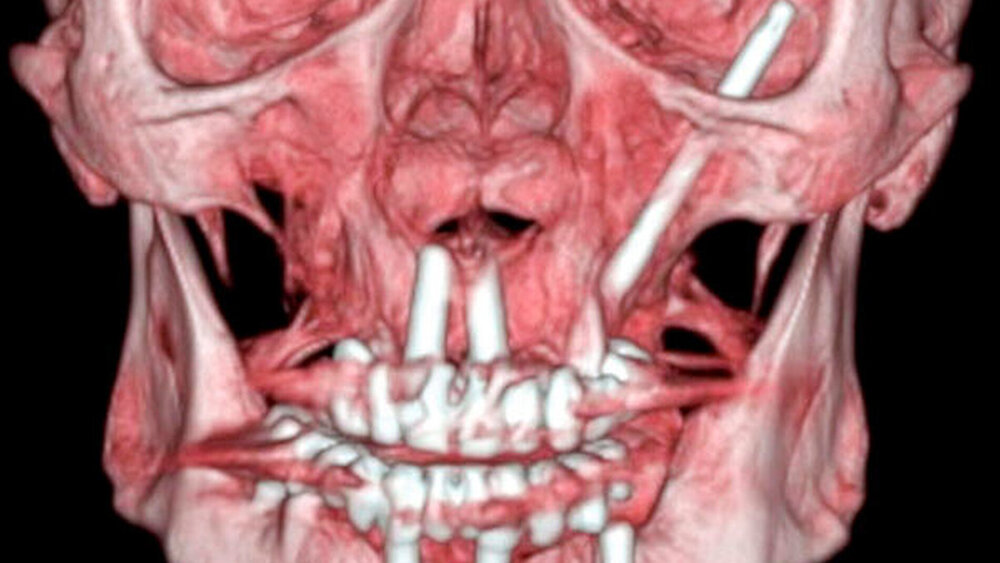

Wegen der unklaren Genese der akuten entzündlichen Veränderungen in der Orbital- und in der Periorbitalregion wurde eine CT- Diagnostik des Schädels mit Kontrastmittelgabe zum Ausschluss einer akuten retrobulbären Raumforderung veranlasst. Hierbei fand sich ein hochgradiger Verdacht auf eine Abszedierung in der rechten Orbita mit dem klinischen Bild von Protrusio bulbi und entzündlicher Mitreaktion der Augenmuskeln M. rectus lateralis und M. rectus inferior. Diese Veränderungen waren auch der Grund für die Weichteilschwellung am Unterlid. Ein intraorbitales Hämatom ließ sich ausschließen.

Zur weiteren Abklärung erfolgte nach zweidimensionaler Beurteilung die dreidimensionale Rekonstruktion der CT-Daten. Hierbei kamen die röntgenopaken Implantate im Kiefer sehr gut zur Darstellung und konnten in Bezug auf deren anatomische Lage beurteilt werden. Im atrophen Ober- und Unterkiefer zeigte sich ein mittelgradiger horizontaler Knochenabbau mit vertikalen Einbrüchen an allen Implantaten. In der rechten Maxilla regio 016 bestand nach Explantation eines rechtsseitigen Zygoma-Implantats ein circa 2 cm großer Defekt, der, aufgrund der verdrängten Weichgewebe und Lufteinschlüsse sicher bis in die mittlere, zentrale Orbita reichte.

Als auffälliger Nebenbefund fand sich auch auf der linken Seite ein 60-mm-Zygoma-Implantat, das 17 mm in die linke Augenhöhle ragte. Neu aufgetretene Veränderungen oder Behinderungen in diesem Bereich waren vom Patienten subjektiv nicht wahrgenommen worden, die Implantation selbst lag bereits zehn Jahre zurück.